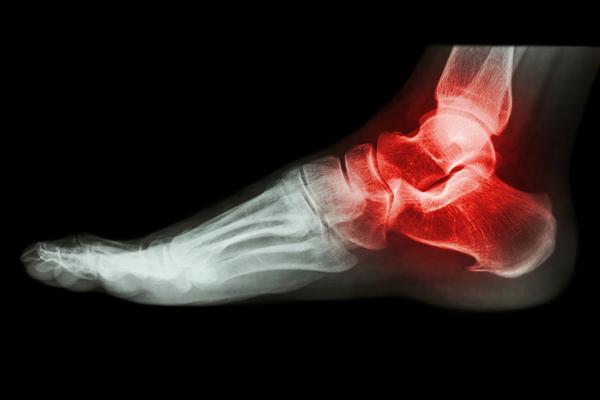

“痛风”是我国较为高发、常见且十分复杂的关节炎类型 , 它是以高尿酸血症作为基础而病发的 。

由于患者体内尿酸水平超标 , 大量尿酸盐结晶析出并堆积在各个关节处 , 特别是皮肤薄弱的关节处更容易沉积尿酸盐结晶 , 最终促使痛风发作 。

通常情况下 , 第一次急性痛风发作 , 多是在夜间、醉酒之后 , 患者会突然出现某一处关节异常疼痛 , 痛感就如同关节被火烧、电灼一般 。

古人将痛风更是称为“白虎历节” , 也就是说在痛风发作时 , 痛感如同老虎啃食关节一般 。 这真是:啊 , 多么痛的领悟!那么问题来了 , 痛风夜间突发、痛感难以忍受 , 患者到底该如何止痛呢?